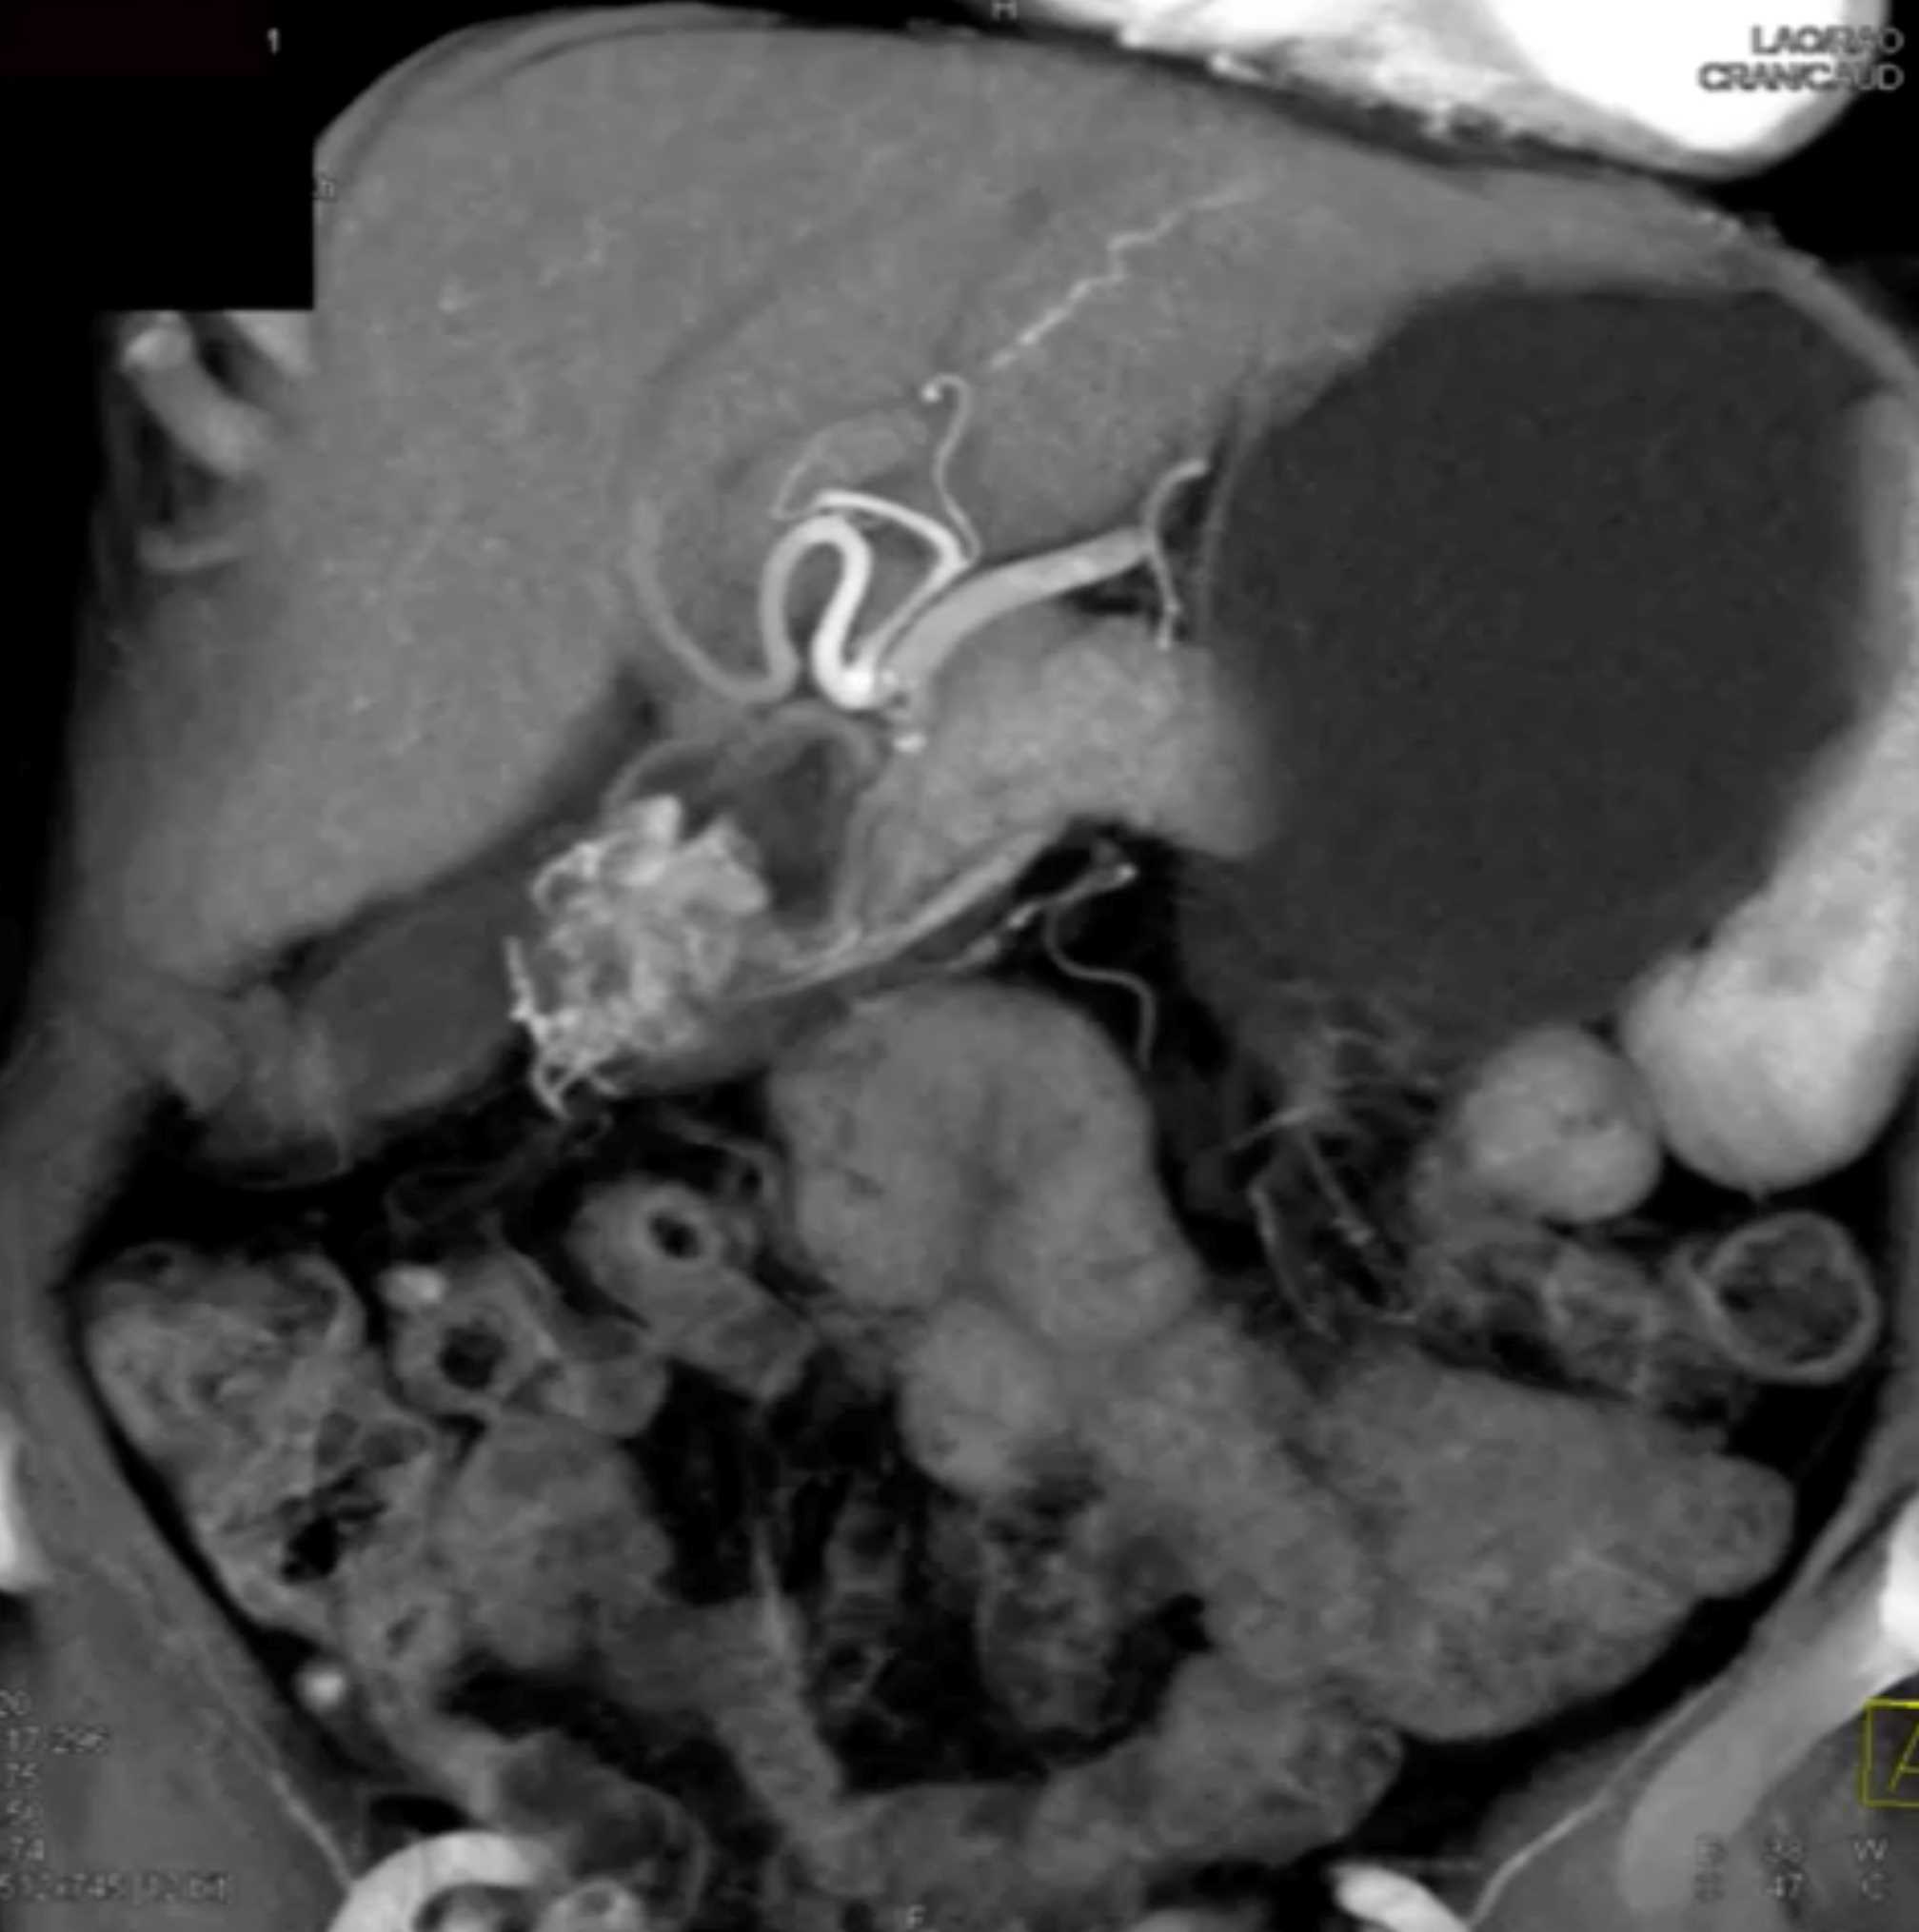

Watermelon Stomach (Gastric Antral Vascular Ectasis)